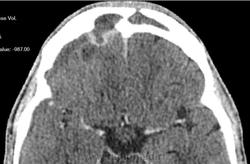

-над лобной, височной и теменной долями правого полушария большого мозга определяется скопление патологического содержимого плотностью до +20HU, размерами 122х14х98мм(V~87см3)- субдуральная эмпиема, размеры ранее описываемого участка гиподенсной плотности в полюсно-базальных отделах правой лобной доли (+25+30Hu), увеличились до 36х11мм. Смещение срединных структур влево до 10мм.

К делу подключились нейрохирурги, больной был экстренно прооперирован. Произведена КПТЧ, удаление субдуральной эмпиемы лобно-височно-теменной области справа, постановки дренажа под ТМО. Также вскрыты передние стенки обоих гайморовых пазух, произведена ревизия лобной пазухи, в пазухи заведены тампоны. По образному выражению нейрохирурга, при вскрытии ТМО получили: "Фонтан гноя". Снимки после операции:

Динамика отчетливо положительная, субдуральное гнойное содержимое практически полностью эвакуировано. Дислокация срединных структур уменьшилась. Определяется постоперационная пневмоцефалия.